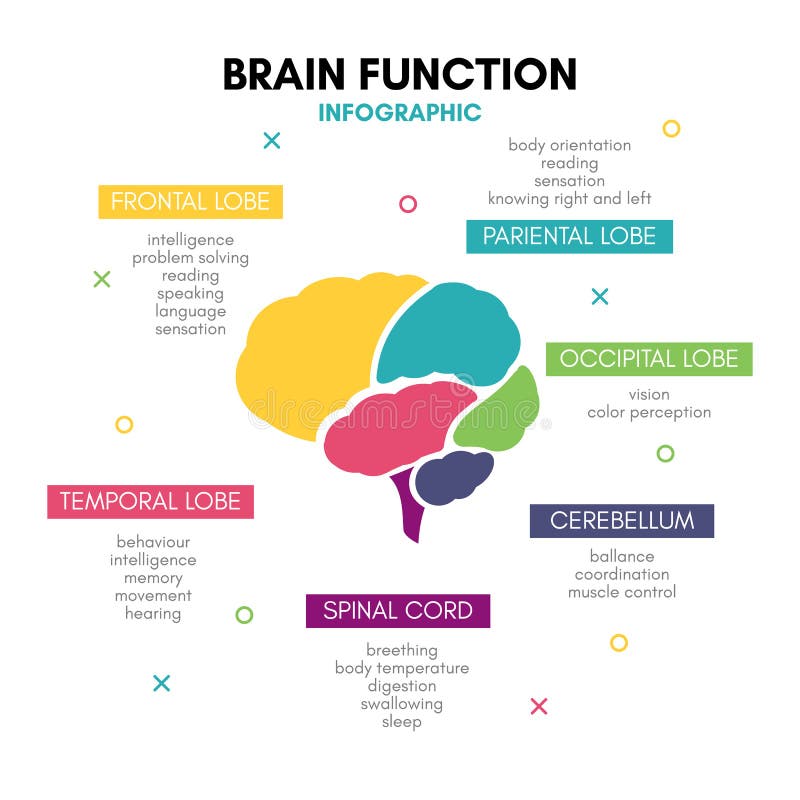

έννοια της τεχνητής νοημοσύνης. άνθρωπος-εγκέφαλος με σύμβολο τεχνητής νοημοσύνης.